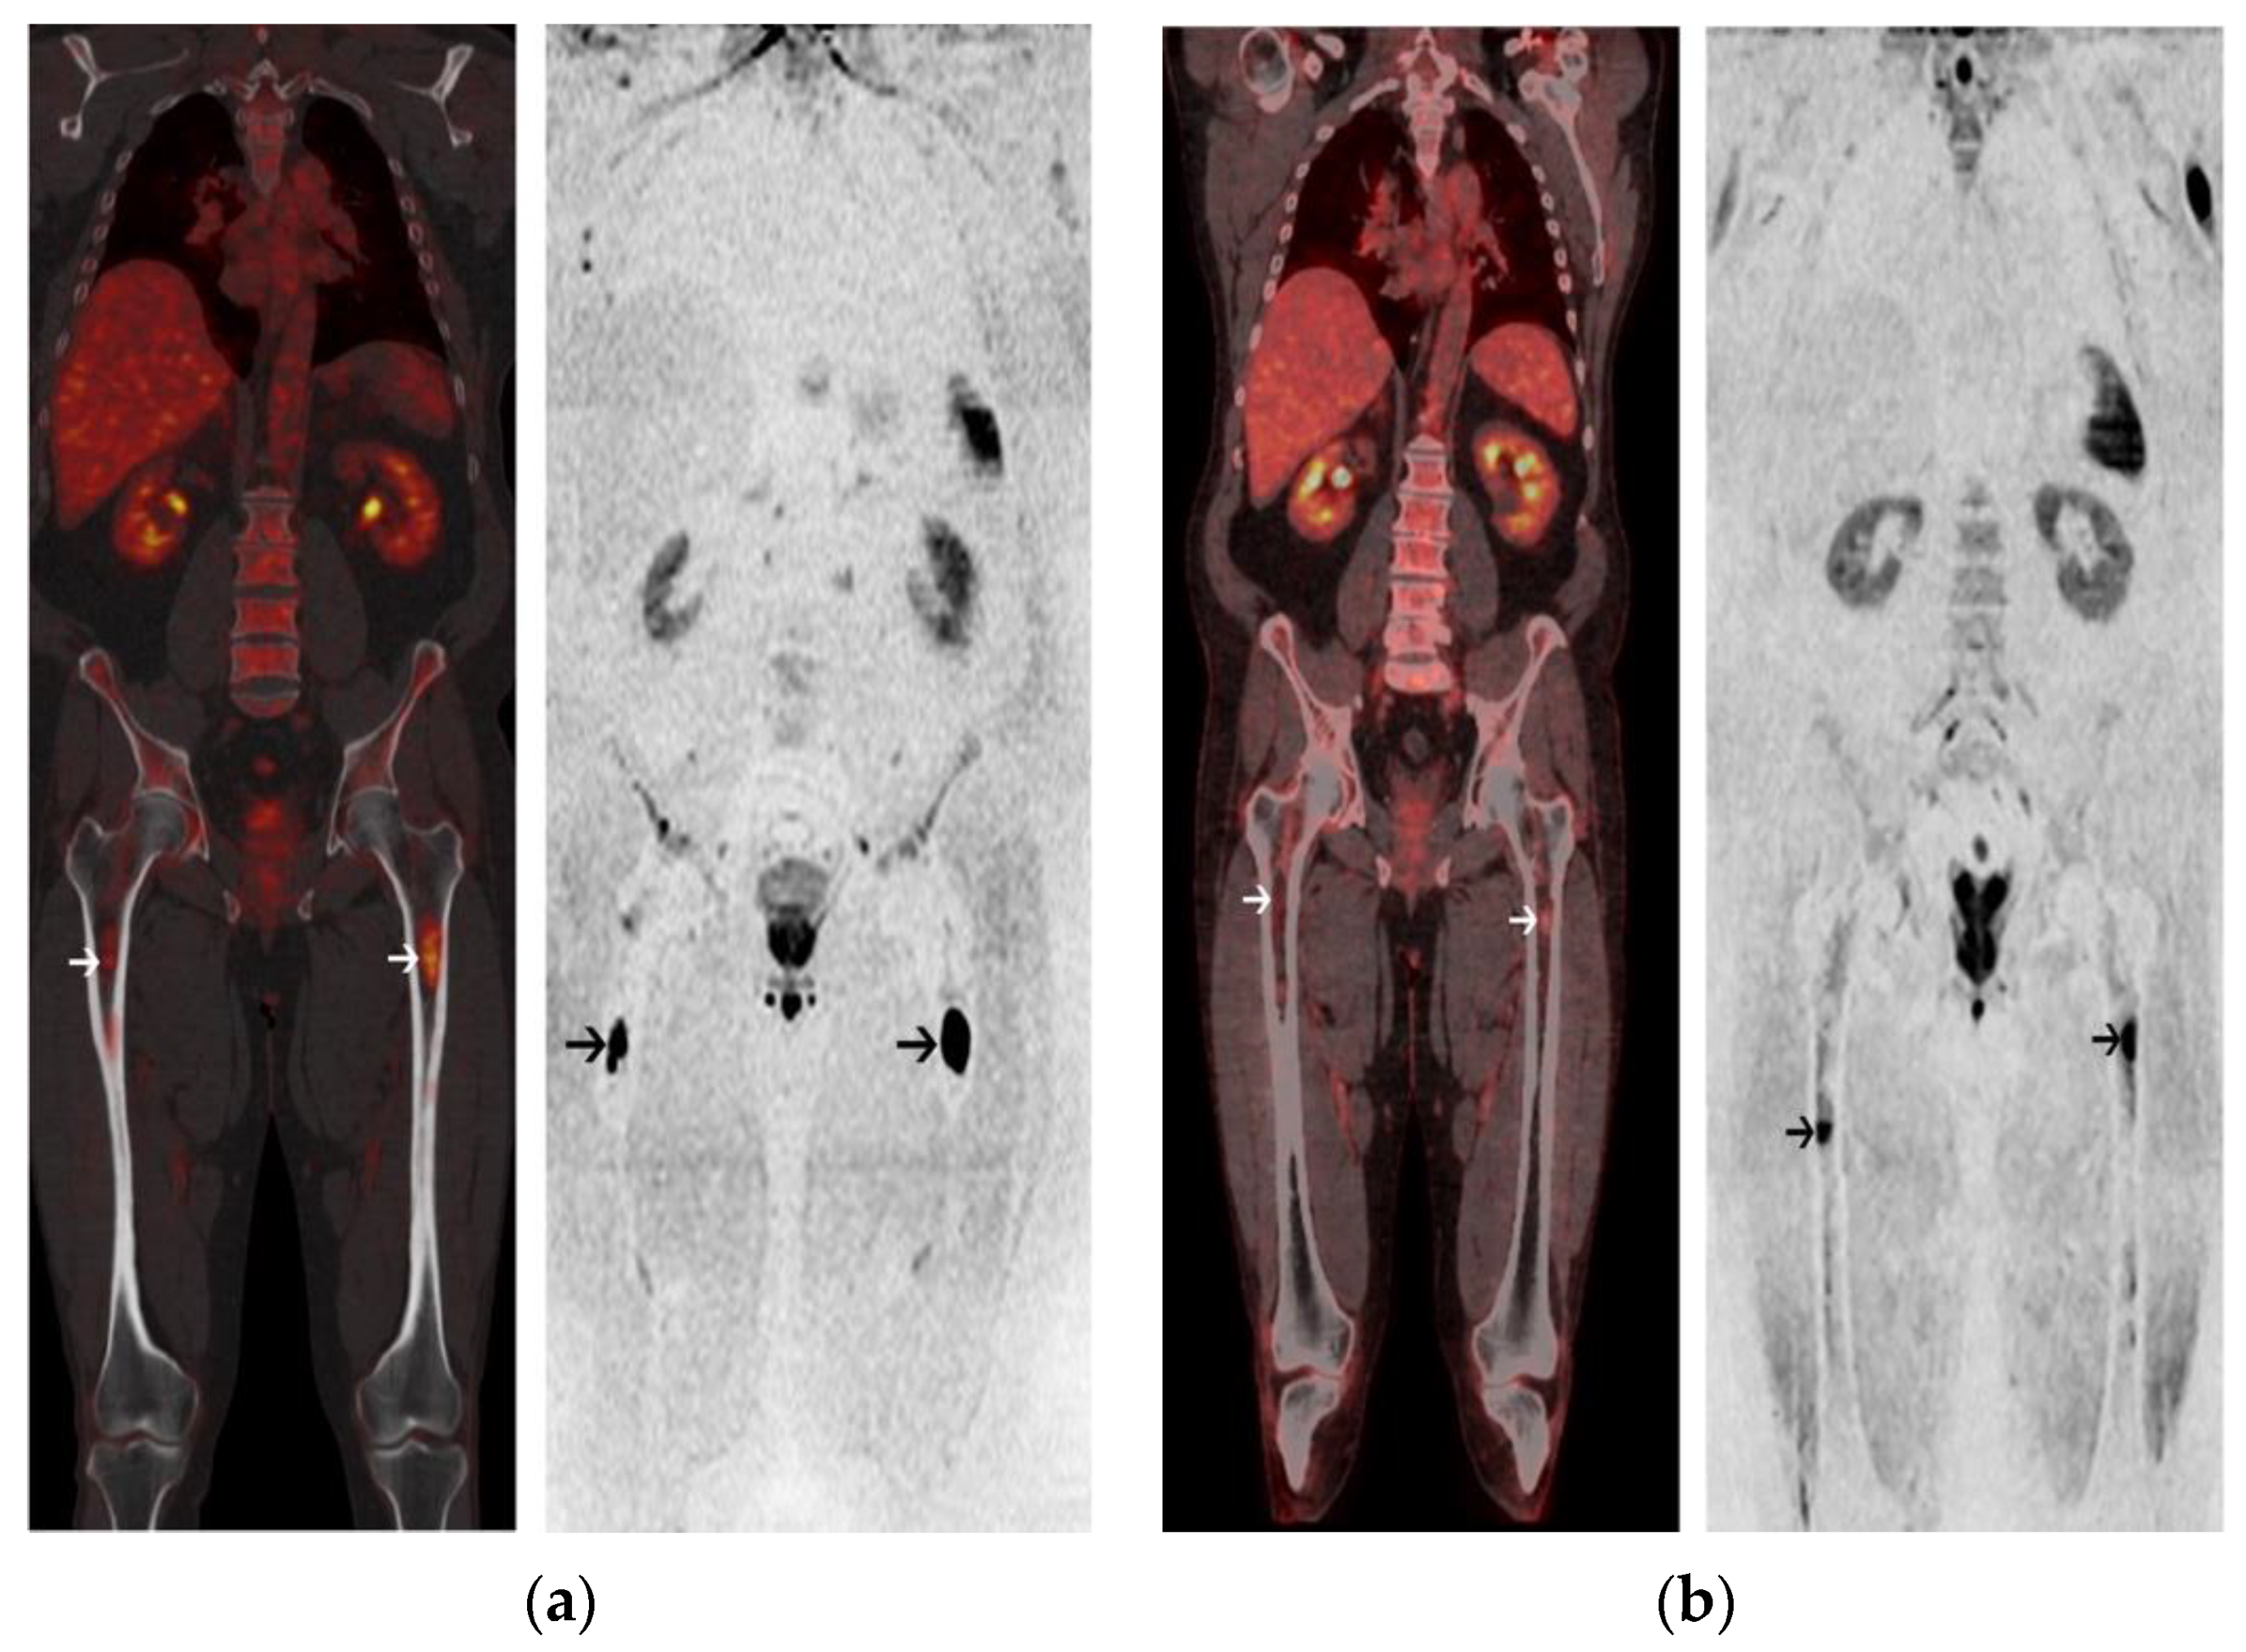

2.2. Post-Induction Chemotherapy Imaging

2.3. Post-ASCT Imaging